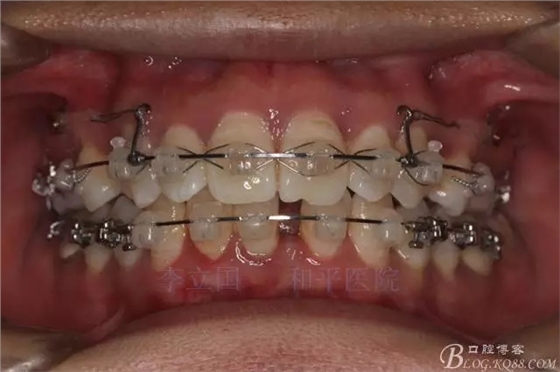

2.Damonclear排齊整平。

3.微種植支抗內(nèi)收上下前牙。

3.上頜應(yīng)用支抗釘。表麻下在56牙槽間隔植入,注意因使用的為鈦合金釘,一直保持植入角度與骨面成60度角,不要垂直植入再改變角度。要求即刻加載,即刻加載力值2盎司。

4.使用長(zhǎng)牽引鉤,使?fàn)恳咏项M骨阻抗中心,防止上頜骨的順時(shí)針旋轉(zhuǎn)。

5.回收過(guò)程中,上下前牙輕搖椅,防止覆合加深。